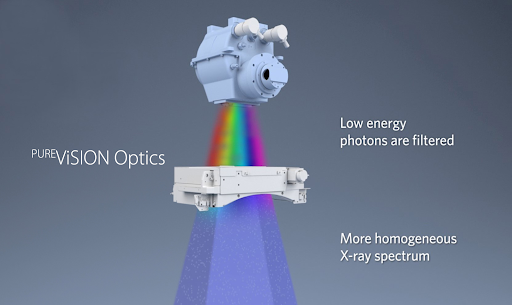

Технология PURE ViSION Optics фильтрует низкоэнергетические фотоны, обеспечивая более однородный спектр, который улучшает качество изображения и снижает дозу облучения пациентов.